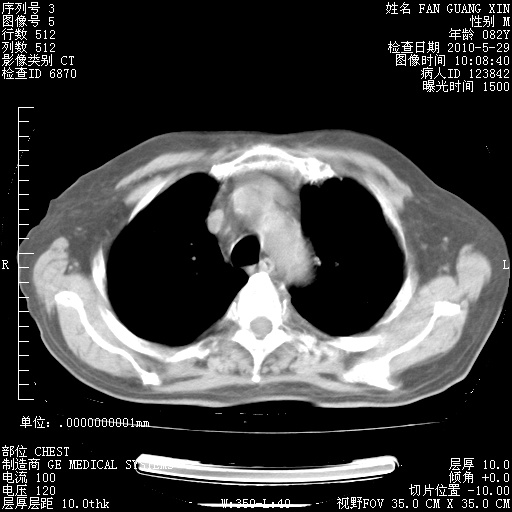

再治疗10天后的肺部CT

肺部体征:呼吸25次/分,心率100次/分,呼吸音增粗。无干湿罗音。

从白细胞总数和中性比例看好像合并感染。肺部纹理好像比上次多,支气管炎?其他感染?

阅读此次胸部CT,肺间质渗出性改变较入院时有吸收。目前从体温、白细胞、中性分叶明显增高,肯定存在细菌感染(发生医院感染哦,若无消化道及泌尿系统等感染的依据,肺部感染可能大)。若你院头孢哌酮舒巴坦钠耐药率较高,同意你的方案,若48小时体温仍高,可考虑使用碳青霉稀类抗菌药物,同时可予超声雾化、注意滴数时加大液体量。白蛋白33.30g/L较低哦,需加强营养等支持治疗。